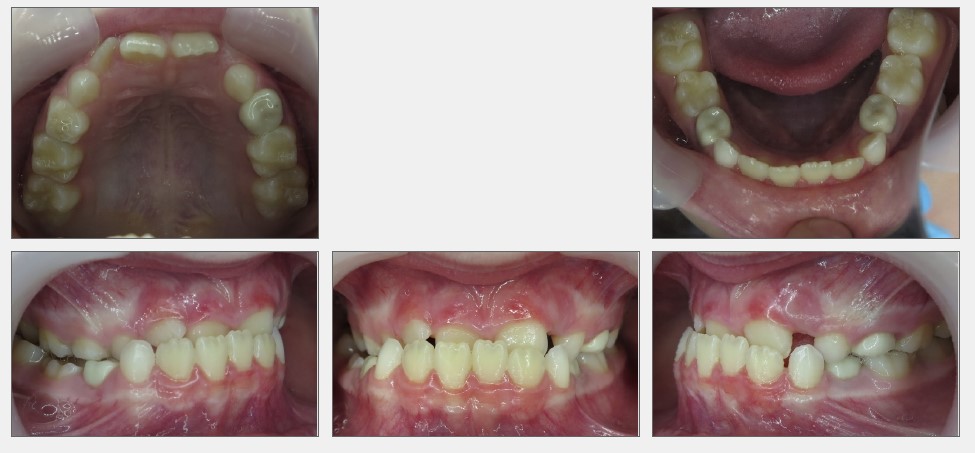

Before crowding